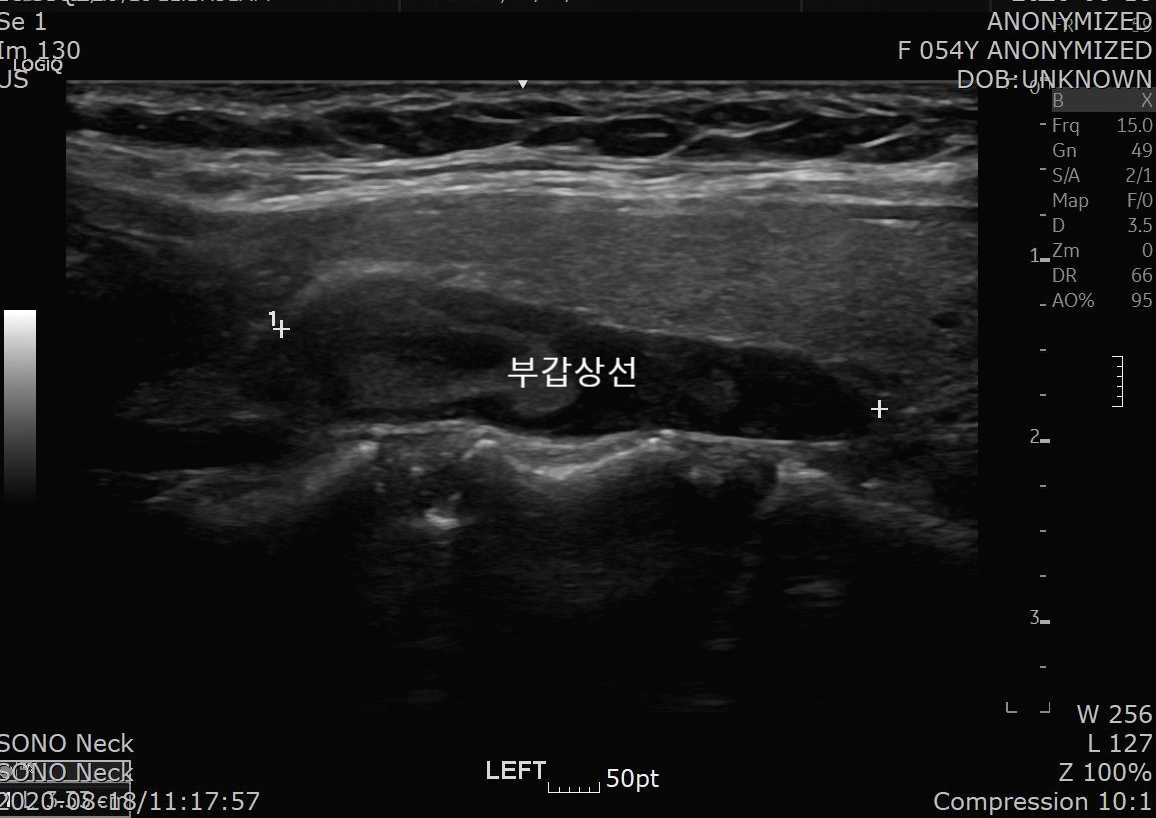

환자분은 갑상선 초음파에서 좌측 갑상선 뒤쪽으로 약 3cm 의 혹이 발견되었습니다.

초음파 소견

About 3.3 cm sized elongated low echoic nodule with internal echogenic portion, posterior to thyroid, left

; R/O Parathyroid tumor

R/O Lymphadenopathy

REC) Check PTH and FNA if necessary

초음파상 좌측 갑상선 뒤쪽으로 3.3cm의 종양이 보이고 부갑상선 종양이 의심되니 부갑상선 호르몬(PTH, ParaThyroid Hormone), 세침흡인검사(FNA, Fine Needle Aspiration)를 시행해 보라는 소견입니다.